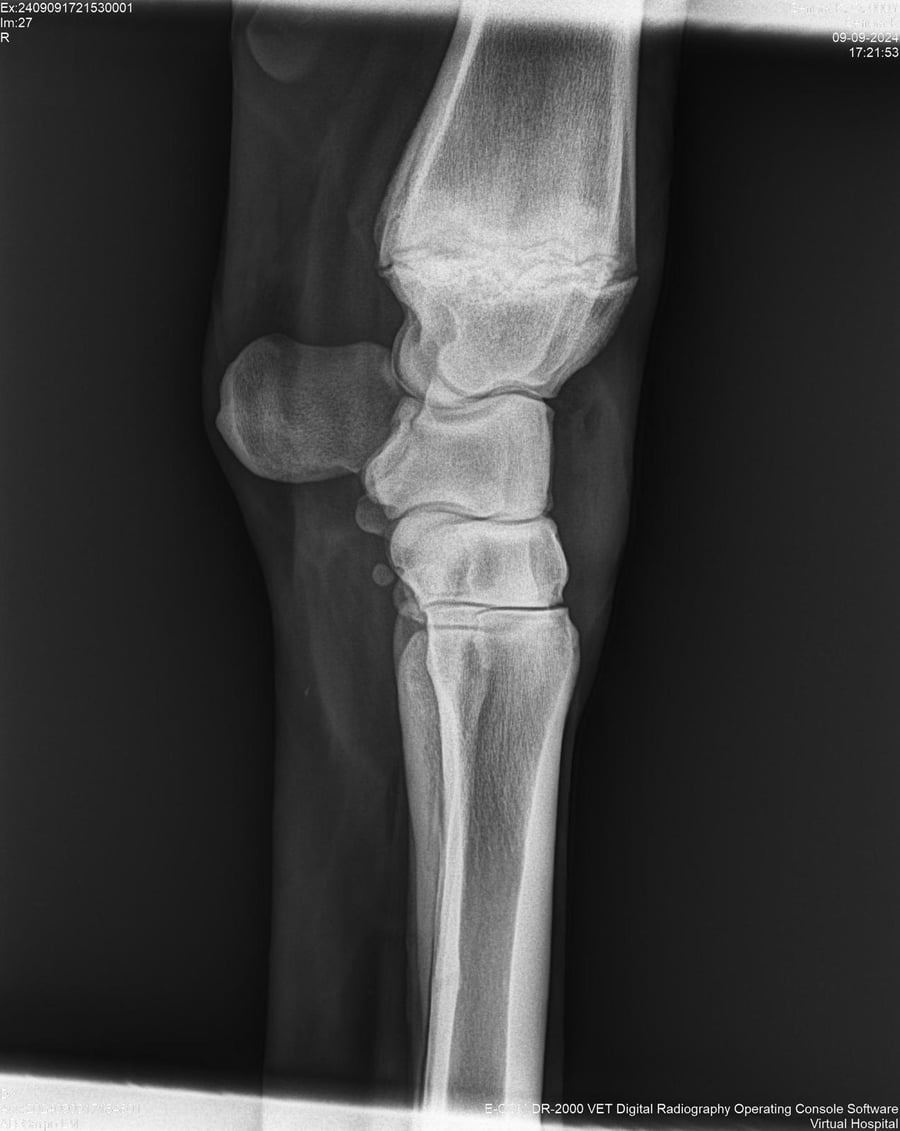

LOTE 44, SEÑORA K

Identificador: #291147-

Generacion 2022